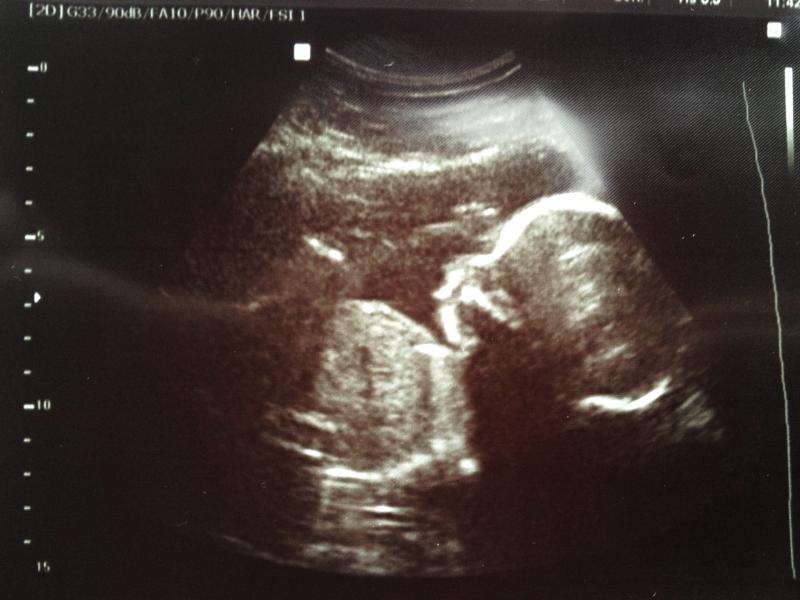

Here are the shots for skull theory:

Attachment 16689

Attachment 16688